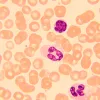

MAGUS Bio 250B biological microscope is an optical instrument used for studying thin transparent and translucent objects. Brightfield microscopy in transmitted light is the main microscopy technique. The microscope can be equipped with additional accessories for using darkfield, phase contrast, and polarization techniques. High-quality optics with additional options to expand its capabilities, easy-to-use mechanics, and smart design make this microscope an excellent choice for lab work, research, and teaching.

The microscope optics in the basic configuration provides magnification from 40 to 1000x. The use of additional eyepieces, if necessary, allows you to increase the upper limit of the magnification range.